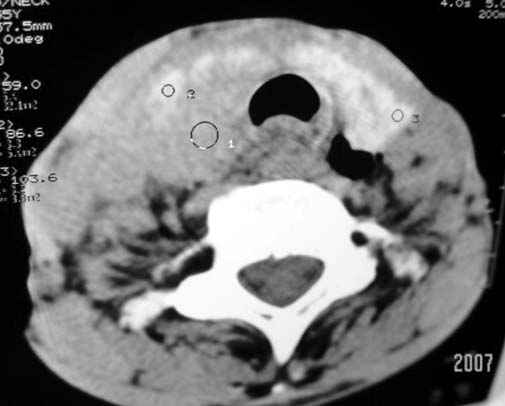

以下是引用dyqct在2007-4-20 16:19:00的发言:[br]考虑:1、左侧梨状窝区破裂伴左颈深、浅部气肿。[br] 2、右侧甲状腺区血肿(请追问病史是否伤及右颈部)。[br] 3、建议病情稳定后增强扫描除外右侧甲状腺腺瘤。